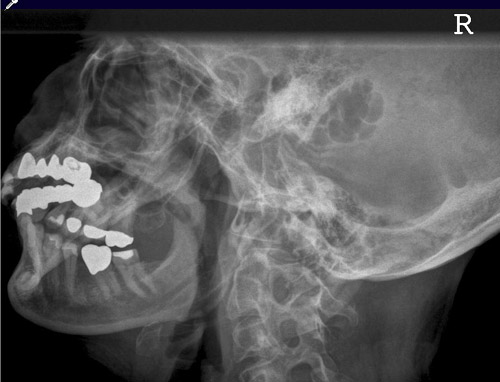

Unterkiefer

Fehler

Das Kieferköpfchen, resp. der Kieferhals sind nicht abgebildet. Es legt sich die obere HWS darüber.

Abhilfe

Der Kopf war zwar richtig seitlich zum Film geneigt, aber, für eine Darstellung des horizontalen Unterkiefers bis zum Eckzahngebiet, mit dem Kinn zu wenig dem Film genähert.